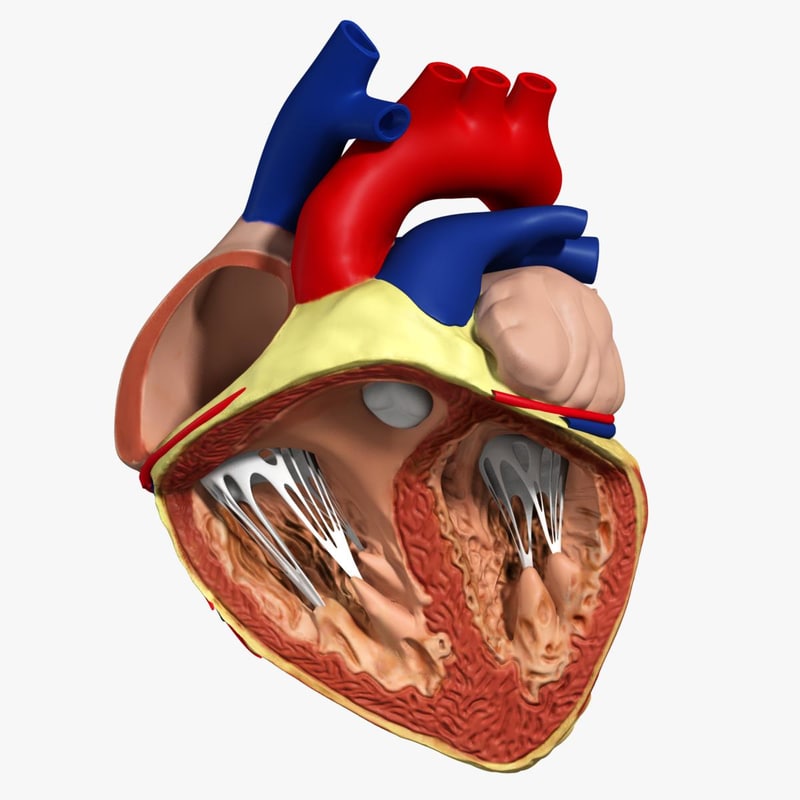

anatomy human heart 3d c4d  Modeled human heart section 3D model - TurboSquid 1657004

Modeled human heart section 3D model - TurboSquid 1657004  Heart by Rustamova on @DeviantArt | Anatomical heart art, Anatomy art, Heart drawing

Human Heart Section 3D model | CGTrader  human heart - internal anatomy 3d model

human heart - internal anatomy 3d model  3D Illustration Human Heart 3D Images - Iwish Iwas

Human Heart Cutaway Anatomy 3D model section | CGTrader  Human Heart by Mutantenmaid on DeviantArt